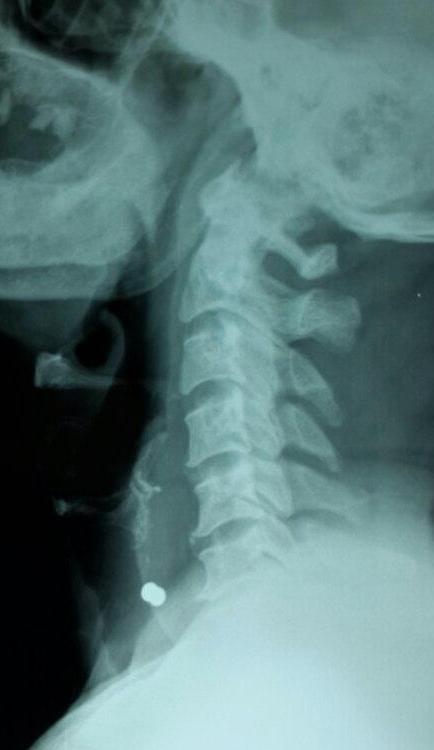

X Ray Neck showed the bullet anterior to the lower border of C6 Vertebra.